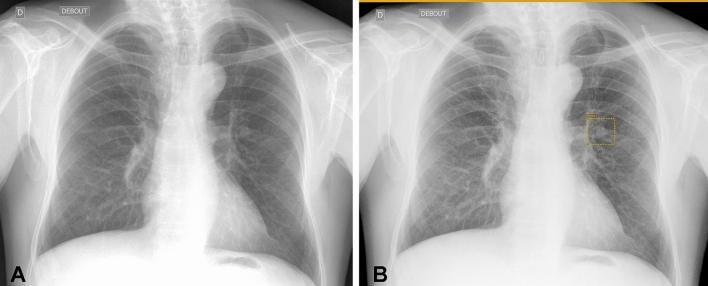

Artificial intelligence (AI) has been a very active research topic over the last years and thoracic imaging has particularly benefited from the development of AI and in particular deep learning. We have now entered a phase of adopting AI into clinical practice. The objective of this article was to review the current applications and perspectives of AI in thoracic oncology. For pulmonary nodule detection, computer-aided detection (CADe) tools have been commercially available since the early 2000s. The more recent rise of deep learning and the availability of large annotated lung nodule datasets have allowed the development of new CADe tools with fewer false-positive results per examination. Classical machine learning and deep-learning methods were also used for pulmonary nodule segmentation allowing nodule volumetry and pulmonary nodule characterization. For pulmonary nodule characterization, radiomics and deep-learning approaches were used. Data from the National Lung Cancer Screening Trial (NLST) allowed the development of several computer-aided diagnostic (CADx) tools for diagnosing lung cancer on chest computed tomography. Finally, AI has been used as a means to perform virtual biopsies and to predict response to treatment or survival. Thus, many detection, characterization and stratification tools have been proposed, some of which are commercially available.

人工智能(AI)是近年来非常活跃的研究课题,特别是在胸部影像学领域,AI 技术,尤其是深度学习技术,得到了广泛的应用。现在,我们已经进入了将 AI 应用于临床实践的阶段。本文的目的是回顾 AI 在胸部肿瘤学中的当前应用和前景。在肺结节检测方面,自 21 世纪初以来,计算机辅助检测(CADe)工具已经商业化。深度学习的兴起以及大型注释肺结节数据集的可用性,使得开发出了新的 CADe 工具,每个检查的假阳性结果更少。经典的机器学习和深度学习方法也被用于肺结节分割,从而实现了结节体积和肺结节特征的定量分析。在肺结节特征分析方面,使用了放射组学和深度学习方法。国家肺癌筛查试验(NLST)的数据允许开发几种计算机辅助诊断(CADx)工具,用于在胸部 CT 上诊断肺癌。最后,人工智能还被用作进行虚拟活检以及预测治疗反应或生存的手段。因此,已经提出了许多检测、特征分析和分层工具,其中一些已经商业化。